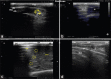

Results: The USG revealed small consolidation areas within an aerated lung lobe, a hypoechoic parenchyma of the entire distal lung lobe, and a hypoechoic-circumscribed structure surrounded by an echogenic wall appeared within the lung tissue in calves that suffered from lobular pneumonia, lobar pneumonia, and lung abscess, respectively. However, subclinical cases showed a small consolidation area in the cranial aspects of the right cranial lung lobe. The ultrasound lung score (ULS) was greater in clinical than in subclinical cases. The BRD-affected calves recorded significant increases in serum TP, globulin, and HP. Meanwhile, serum ALB decreased significantly.